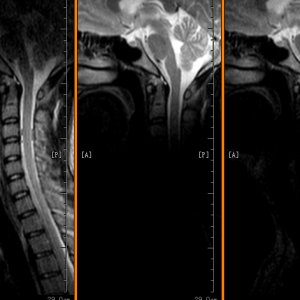

Thần kinh (não, tủy sống, dây thần kinh)

Cơ xương khớp (khớp, chi, cột sống)